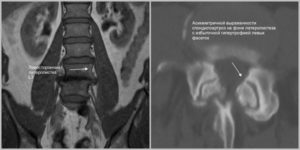

Основные методы диагностики — магнитно-резонансная и компьютерная томография. При неврологических жалобах у пациента (нарушение чувствительности и подвижности конечностей) на МРТ или КТ выявляют наличие трабекулярного отека позвонков.

Самостоятельно определить наличие трабекулярного отека невозможно. Самым действенным способом диагностики служит компьютерная томография. Методика демонстрирует трехмерное изображение травмированного района, позволяет лицезреть окружающие припухлость зоны. Наличие видимых признаков протекания патологии позволяет получить направление на дополнительные анализы.

- рентгенологический осмотр — выявляет наличие излишней жидкости, травм позвоночника;

- проведение МРТ — позволяет увидеть патологические процессы, поражающие мягкие ткани организма;

- магнитно-резонансную томографию (МРТ), которая позволит определить точную локализацию очагов скопления экссудата;